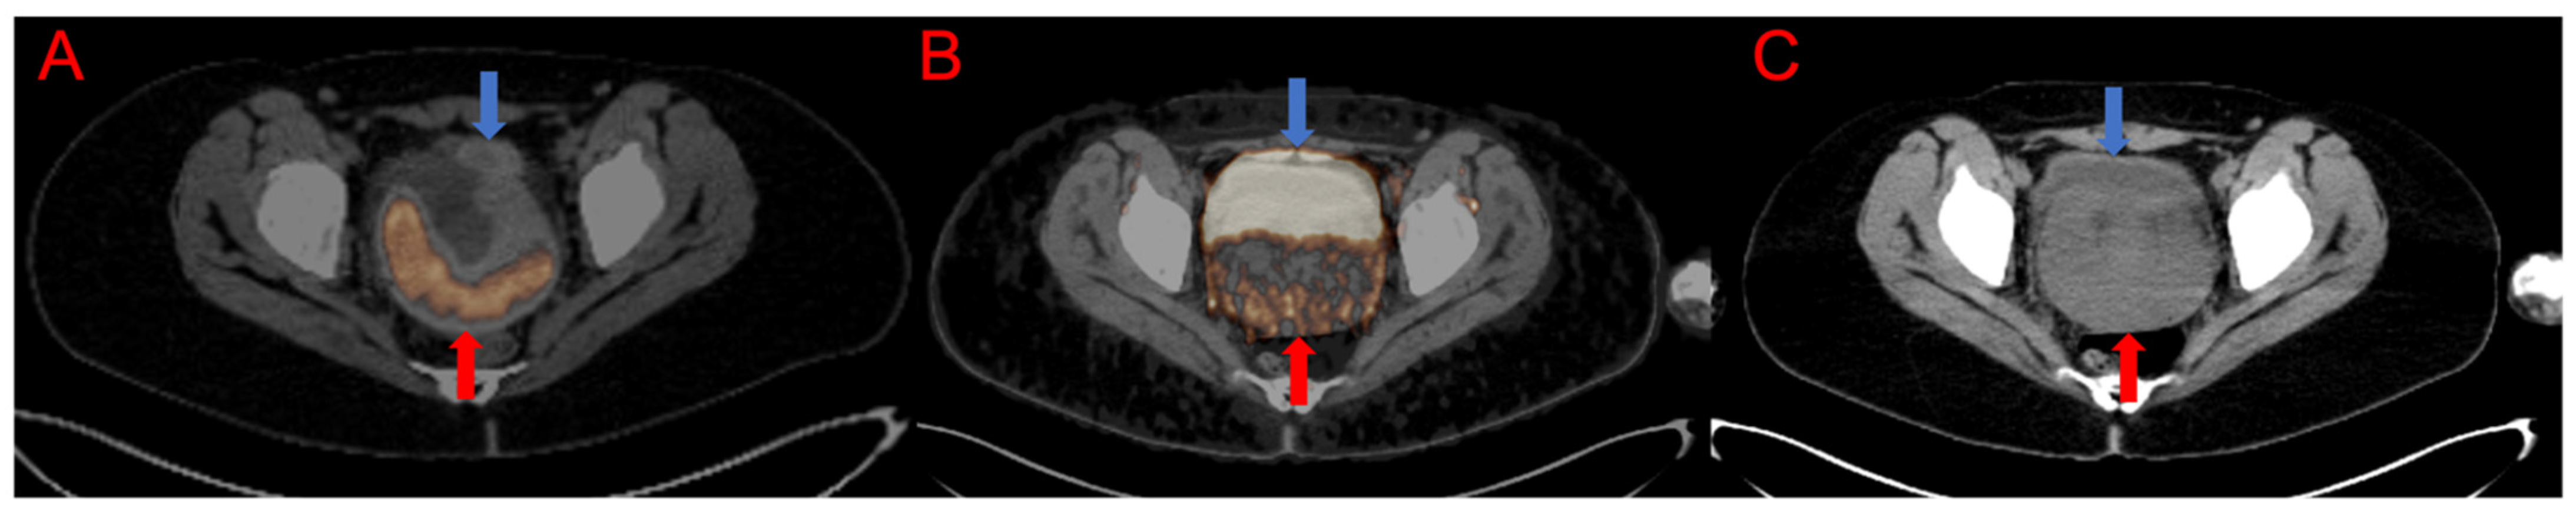

3.1. Qualitative and Semiquantitative Analysis of the PET/CT Images